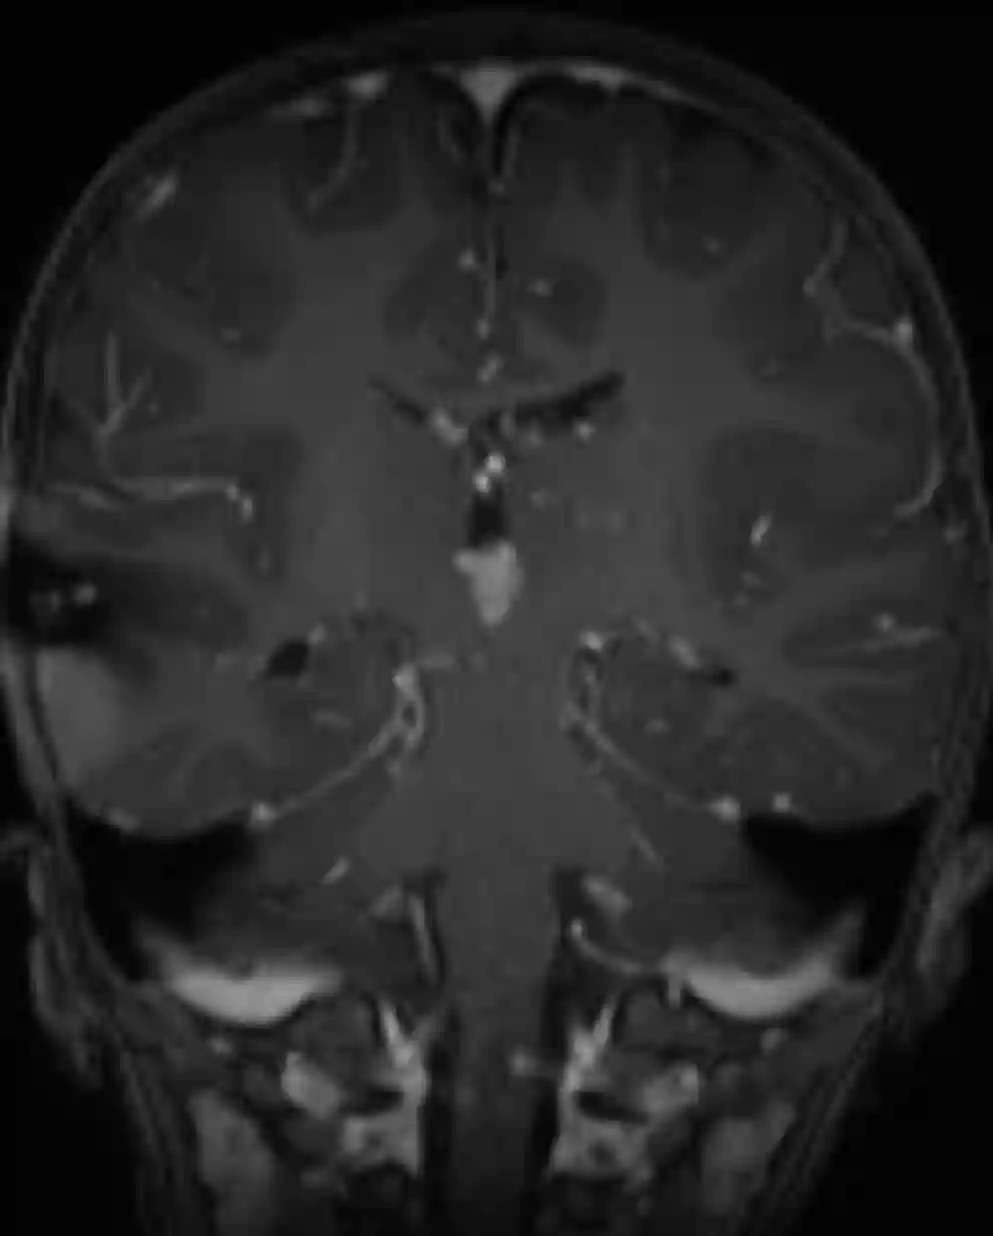

Der Goldstandard in der Darstellung von Plexuspapillomen ist die MRT Bildgebung. Im MRT zeigen sich Plexuspapillome als gut definierte extra-axiale Läsion mit Farnkrautwedel-artigen Projektionen, mit einer Kontrastmittelaufnahme und ohne Invasion des Gehirnparenchyms. In seltenen Fällen können Plexuspapillome nur wenig oder kein Kontrastmittel aufnehmen[^3].

Coronares MRT Bild eines Patienten mit einem Plexuspapillom im dritten Ventrikel.Coronares MRT Bild eines Patienten mit einem Plexuspapillom im dritten Ventrikel.

Coronares MRT Bild eines Patienten mit einem Plexuspapillom im dritten Ventrikel.